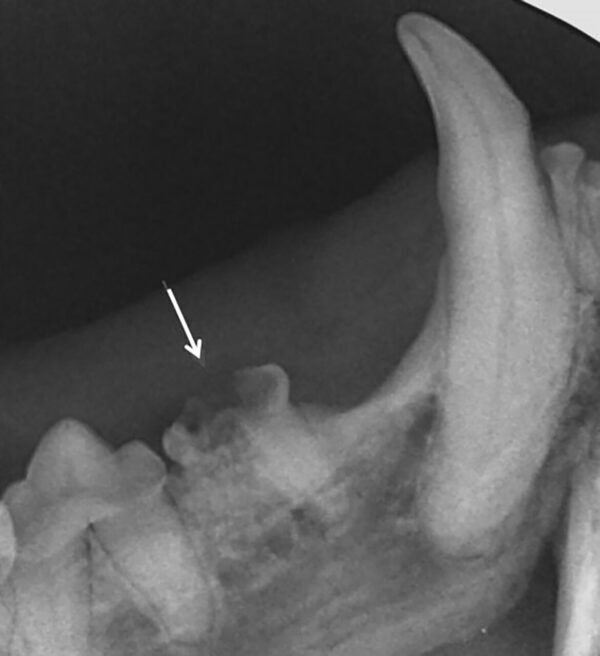

- Grado 4 (PD4): pérdida del soporte óseo mayor de un 50 % (imagen 9).

Además de permitirnos evaluar el grado de enfermedad periodontal, también hace posible seleccionar el mejor tratamiento en función de su patología y las posibles complicaciones, como las fracturas mandibulares iatrogénicas en perros de talla pequeña con enfermedad periodontal PD4 (imágenes 10 y 11).